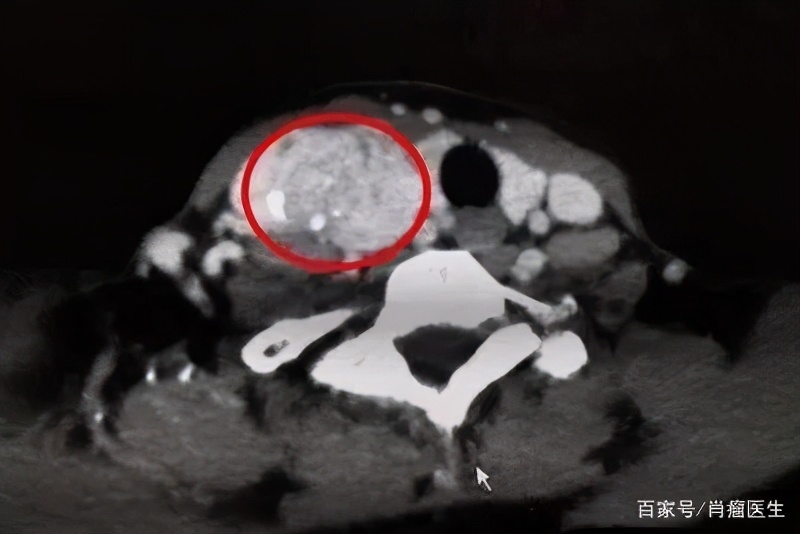

经过检查,结果发现左侧复发了个很大的结节,将近5厘米大,右侧还有一个小结节。王小平主任指出,虽然这次结节已经很大了,但良性的可能性还是比较大的。